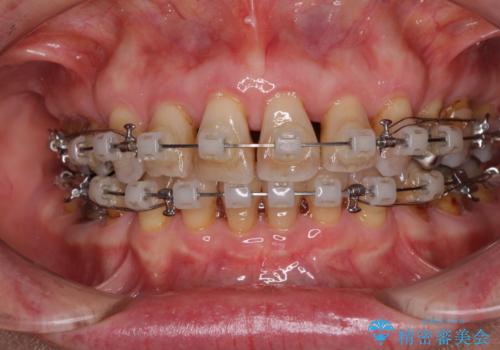

- 口元の突出感と歯の色を気にして来院された患者様です。

口元を引っ込めるために上下左右第一小臼歯4本を抜歯し、ワイヤー矯正を行うこととしました。

歯の色はホワイトニングかセラミッククラウンで対応することとしましたが、ブラックトライアングルが目立つことが予想されたため、目立つ範囲をオールセラミッククラウンで補綴することとしました。